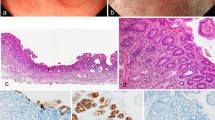

The clinical information of 18 patients with Hp-uninfected DGCs (median age 57 years; range 29–78) and nine subjects without Hp infection (median age 44 years; range 28–77) was collected (Table 1). Sixty-seven percent of patients with DGC had a smoking history, and 33% were current smokers (Table 2). Fifty percent of patients with DGC had alcohol consumption habit. Among the 18 patients, 16 were diagnosed with intramucosal DGC (median age 60 years; range 29–73) and two with advanced DGC. Sixteen intramucosal DGCs were found as flat pale areas upon endoscopy, all of which were resected endoscopically and were found to contain an SRCC component. One DGC localized in the gastric cardia consisted of a mixture of SRCC and PDA components (Fig. 1a and lower panels of Fig. 1b), and the remaining 15 DGCs localized near the gastric angle were ‘pure’ SRCCs scattered around the neck of the gland (Fig. 1a and upper panels of b). These intramucosal ‘pure’ SRCCs had a low proliferation capacity, with a median Ki-67 labeling index of 2.4% (range 0–15.4%). Five cases with intramucosal ‘pure’ SRCC showed no progression over 2–5 years according to endoscopic image review (Fig. 2).

Clinicopathological features of 18 Hp-uninfected DGCs. a Tumor locations and pathological features. Sixteen cases of intramucosal DGC and two cases of advanced DGC were sampled. The red dots represent intramucosal DGCs. Fifteen of sixteen intramucosal DGCs were concentrated near the gastric angle and were 'pure' SRCCs with reduced E-cadherin immunoreactivity. One cardiac intramucosal DGC consisted of SRCC and PDA components with maintained E-cadherin immunoreactivity. Green ovals represent advanced DGCs. Advanced DGCs consisted of SRCC and PDA components with reduced E-cadherin immunoreactivity. b Representative endoscopic and histological images of intramucosal DGC cases. Upper panels: images of case 5. A pale flat lesion was observed at the anterior wall of the gastric antrum, close to the gastric angle, upon endoscopy (yellow arrowhead). H&E staining of the endoscopic submucosal dissection specimen showed that SRCCs were confined to the proliferative zone of the mucosa. Immunohistochemistry for E-cadherin showed weak immunoreactivity in SRCCs. Immunohistochemistry for Ki-67 showed only a few SRCCs positive for nuclear staining. Lower panels: images of case 13. A pale flat lesion was observed at the greater curvature of the gastric cardia upon endoscopy (yellow arrowhead). H&E staining of the endoscopic submucosal dissection specimen showed SRCCs and PDAs in the mucosa. Immunohistochemistry for E-cadherin showed almost the same immunoreactivity in carcinoma cells as in surrounding epithelial cells. Immunohistochemistry for Ki-67 showed that all carcinoma cells were negative for nuclear staining. Scale bar indicates 50 µm